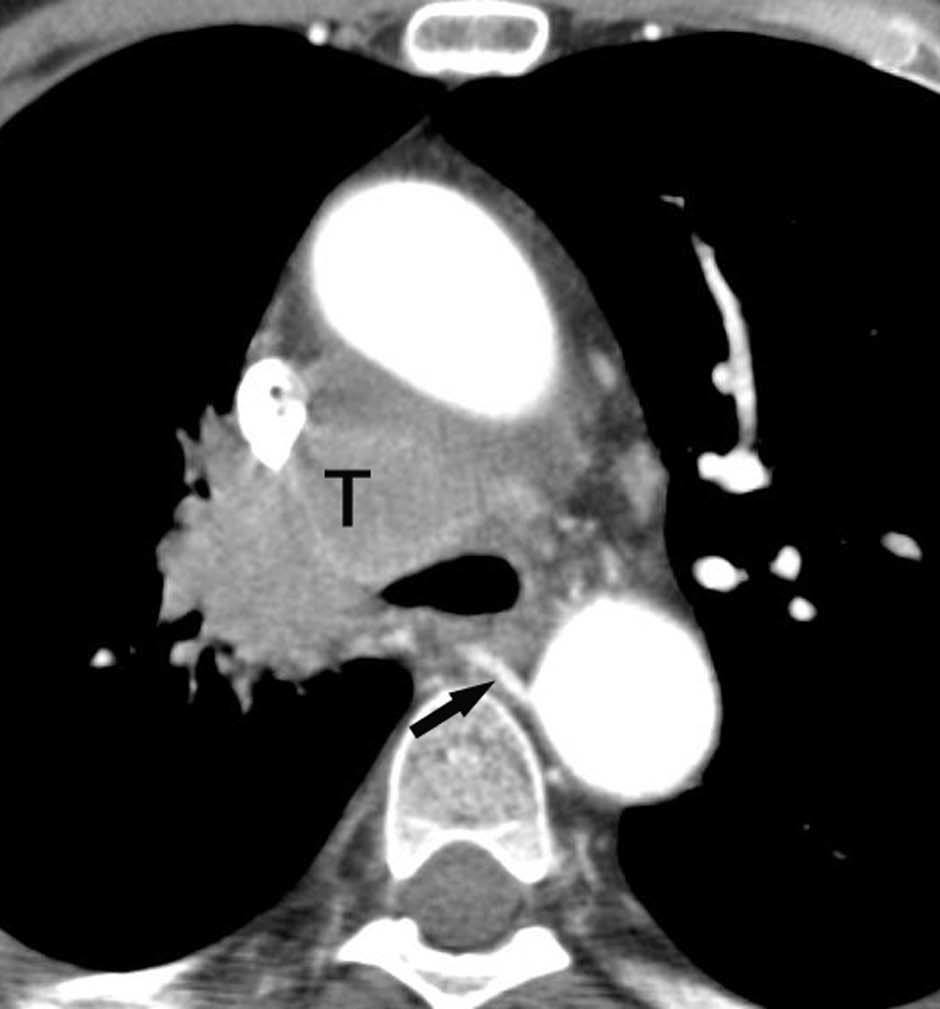

El estadio tumoral (T) se basa en el tamaño, localización y relación con las estructuras adyacentes valorado mediante TC. Los tumores T1 son aquellos de 3 cm o menores en su diámetro mayor, rodeados de pulmón y que no invaden la pleura visceral ni los bronquios principales, mientras que los T2 son lesiones mayores de 3 cm, o aquellas que invaden la pleura visceral o al bronquio principal a más de 2 cm de la carina o que condicionan atelectasia o neumonitis obstructiva que no afecte a todo el pulmón. La diferenciación entre ambos estadios tumorales suele ser sencilla mediante TC, salvo la afectación de la pleura visceral, aunque esta no tiene un impacto importante en el manejo clínico. El tumor T3 viene determinado por la infiltración de estructuras vecinas potencialmente resecables, como la pared torácica, diafragma, pleura mediastínica, pericardio parietal o si el tumor está situado a menos de 2 cm de la carina (fig. 1). Los tumores T4 son aquellos que no pueden ser resecados porque engloban a estructuras vitales, invaden el corazón, grandes vasos, esófago o cuerpos vertebrales (fig. 2) o en los que existe un nódulo o nódulos en el mismo lóbulo del tumor. Además de definir la T, es importante reflejar las particularidades de la infiltración de estructuras en vecindad que puedan modificar la actitud terapéutica. Por ejemplo, cambiará la estrategia quirúrgica según el tipo de bronquio afecto o la estructura mediastínica infiltrada, si es sólo la grasa, o un vaso; cuando existe neumonitis o atelectasia secundaria a un tumor central, la planificación del campo de radioterapia dependerá del límite entre la masa y la repercusión pulmonar.

Fig. 2.--T4. (A) Corte axial de tomografía computarizada (TC) torácica con contraste. Tumor hiliar derecho que infiltra la arteria pulmonar derecha, la vena cava superior y engloba al bronquio intermediario. (B) Reconstrucción coronal oblicua, longitudinal al eje de la arteria pulmonar derecha, que muestra cómo engloba el tumor a la rama del truncus superior (flecha blanca) e inferior (flecha negra).